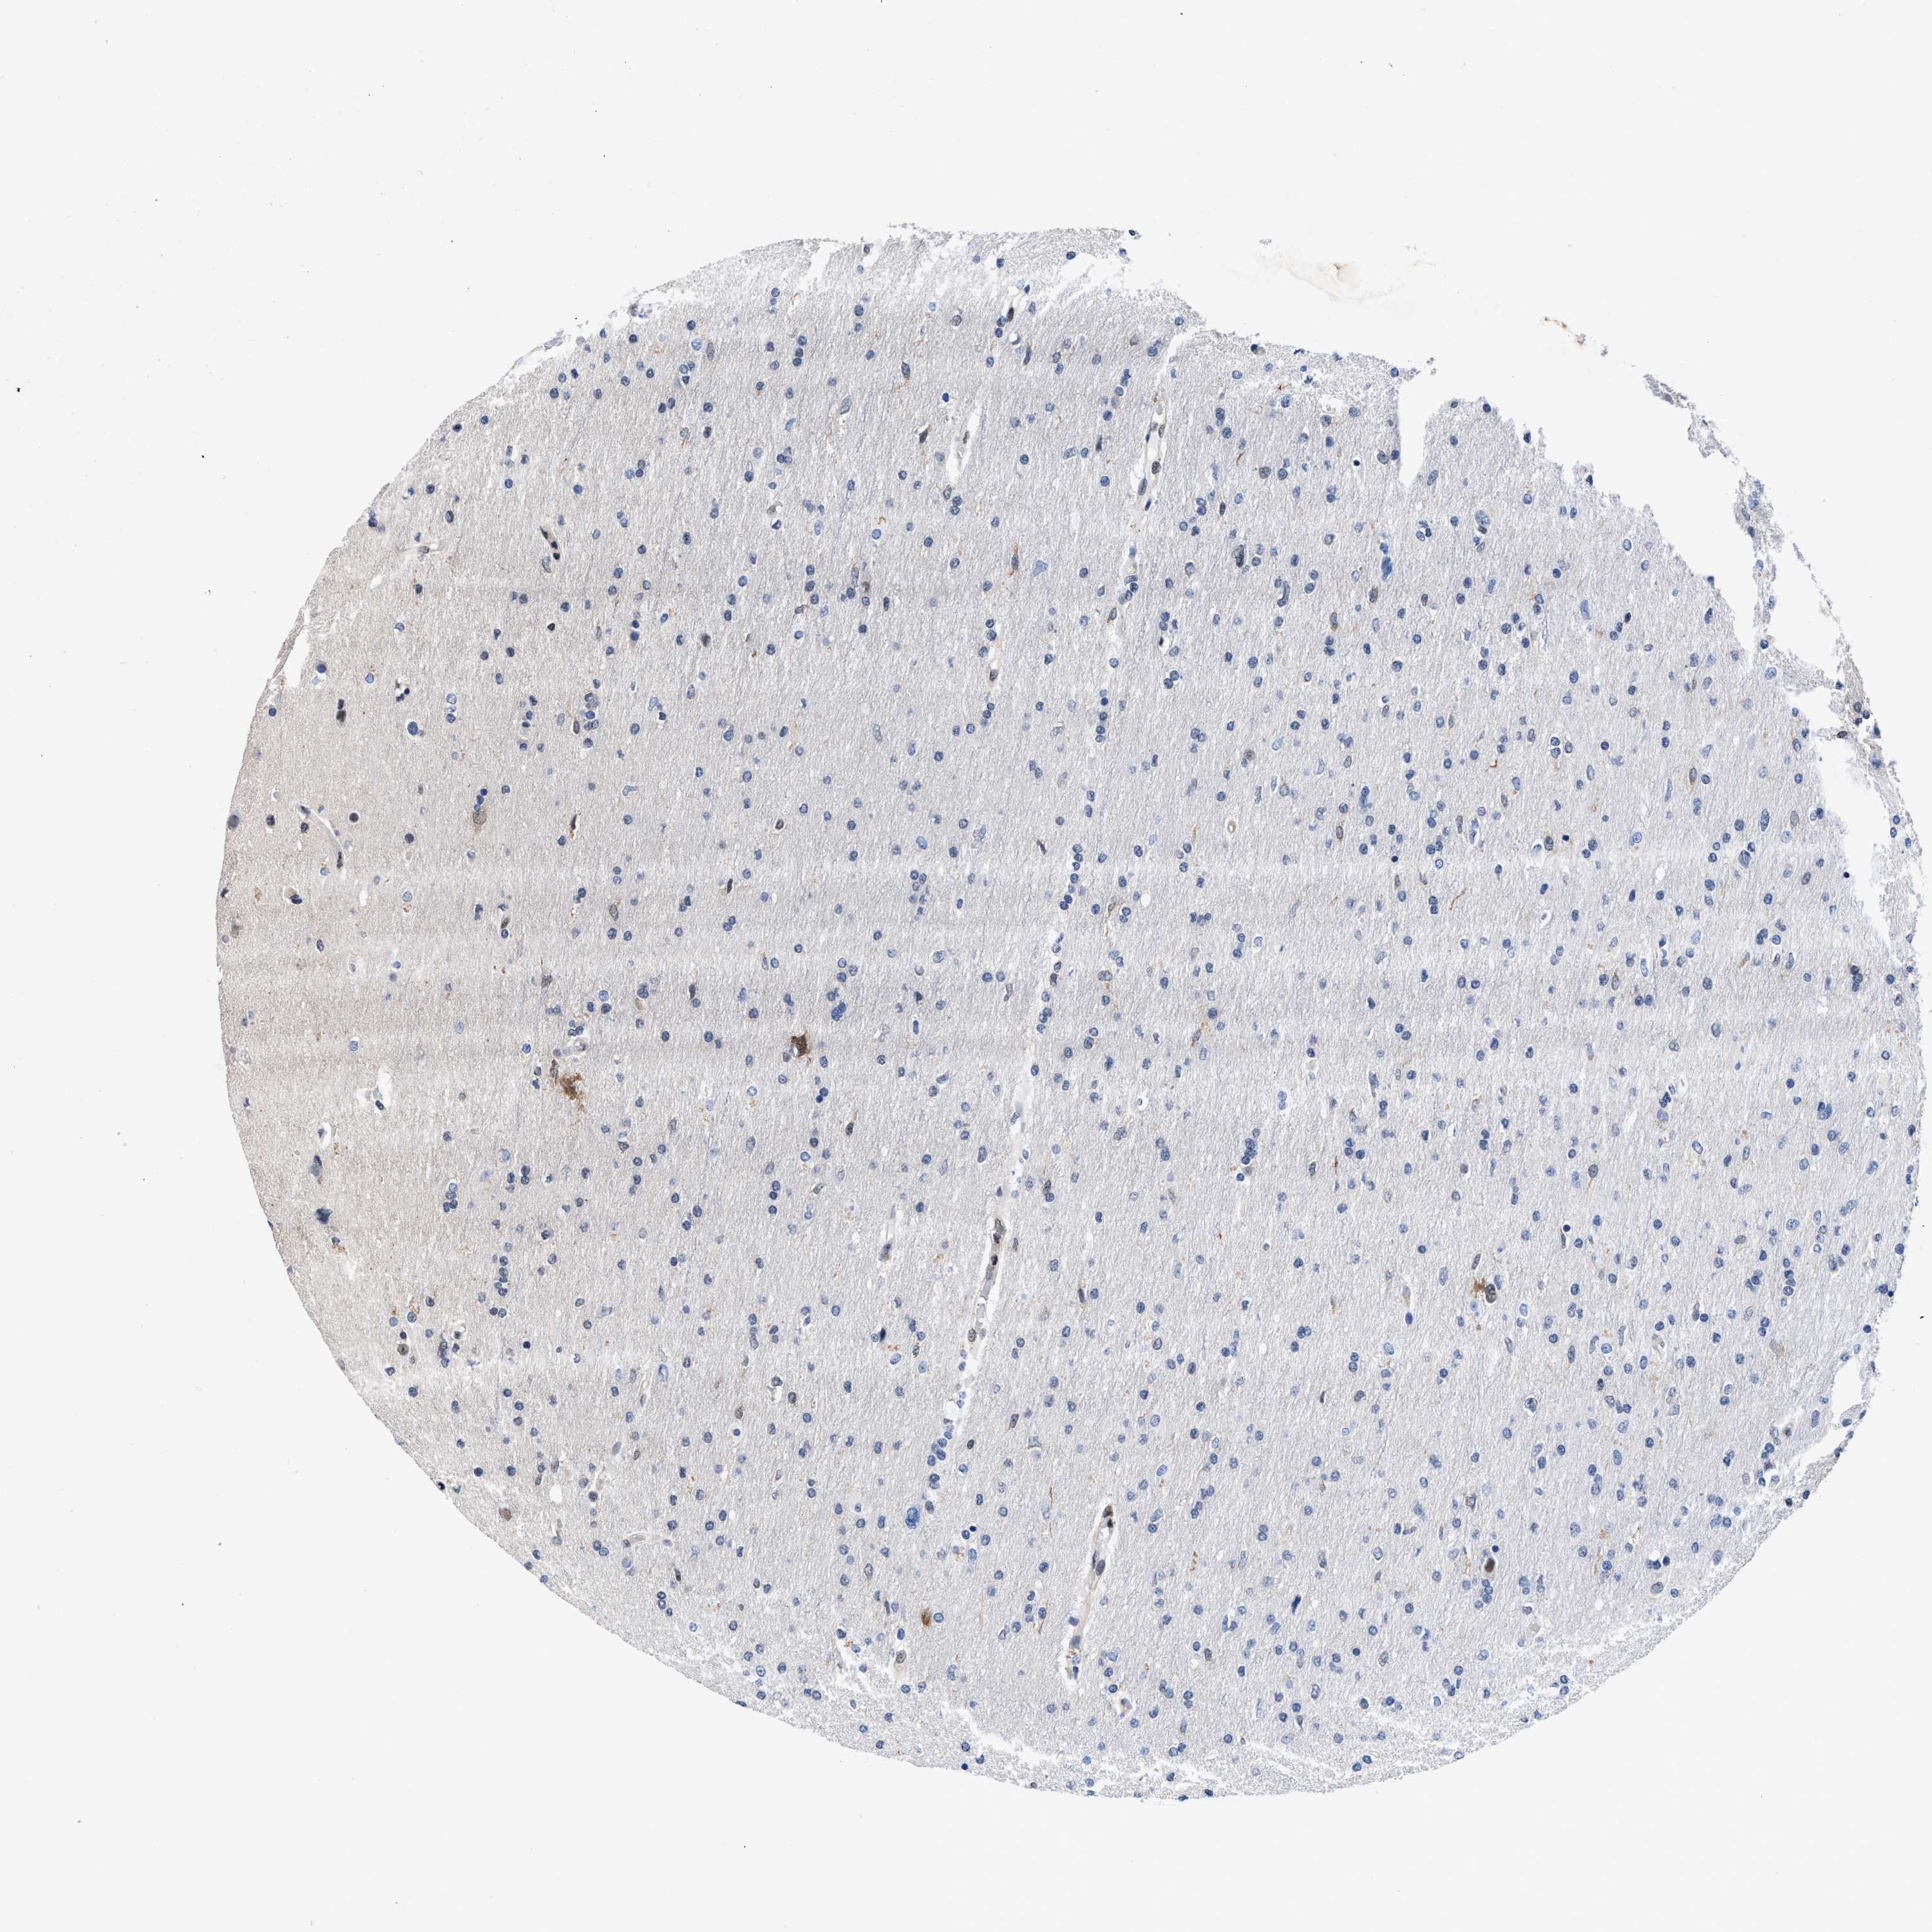

GLIOMA - Protein expressioni

A mouse-over function shows sample information and annotation data. Click on an image to view it in a full screen mode. Samples can be filtered based on level of antibody staining by selecting one or several of the following categories: high, medium, low and not detected. The assay and annotation is described here.

Note that samples used for immunohistochemistry by the Human Protein Atlas do not correspond to samples in the TCGA dataset.

Antibody stainingi

Antibody staining in the annotated cell types in the current human tissue is reported as not detected, low, medium, or high, based on conventional immunohistochemistry profiling in selected tissues. This score is based on the combination of the staining intensity and fraction of stained cells.

Each image is clickable and will lead to virtual microscopy that enables deeper exploration of all samples and also displays staining intensity scores, fraction scores and subcellular localization as well as patient and tissue information for each sample.

HPA022434

HPA022953

HPA022959

HPA028758

CAB007783

Glioma, malignant, High grade

Glioma, malignant, Low grade

Glioblastoma, NOS